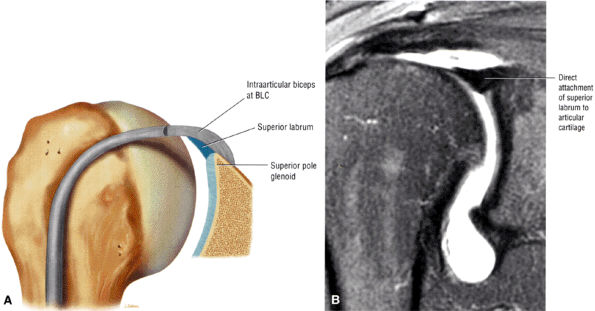

FIGURE 8.75 ● (A) Type 1 BLC with superior labrum firmly attached to the superior pole of the glenoid. The type 1 BLC may be seen in the posterior wedge labrum and the anterior wedge labrum. (B) Coronal FS PD FSE image showing a type 1 BLC with a firm attachment of the superior labrum to the articular cartilage of the superior pole of the glenoid.

FIGURE 8.76 ● (A) Type 2 BLC with a normal sulcus or separation of the free edge of the superior labrum from the superior pole of the glenoid. A type 2 BLC would be seen in the superior wedge labrum and combination superior and anterior wedge labrum. (B) Type 2 BLC with a fluid-filled sulcus separating the superior labrum from the adjacent articular cartilage of the glenoid. The superior labrum is triangular in cross-section. The sulcus may become more prominent with external rotation; however, its medial-to-lateral separation should not exceed 5 mm. Coronal MR arthrogram.